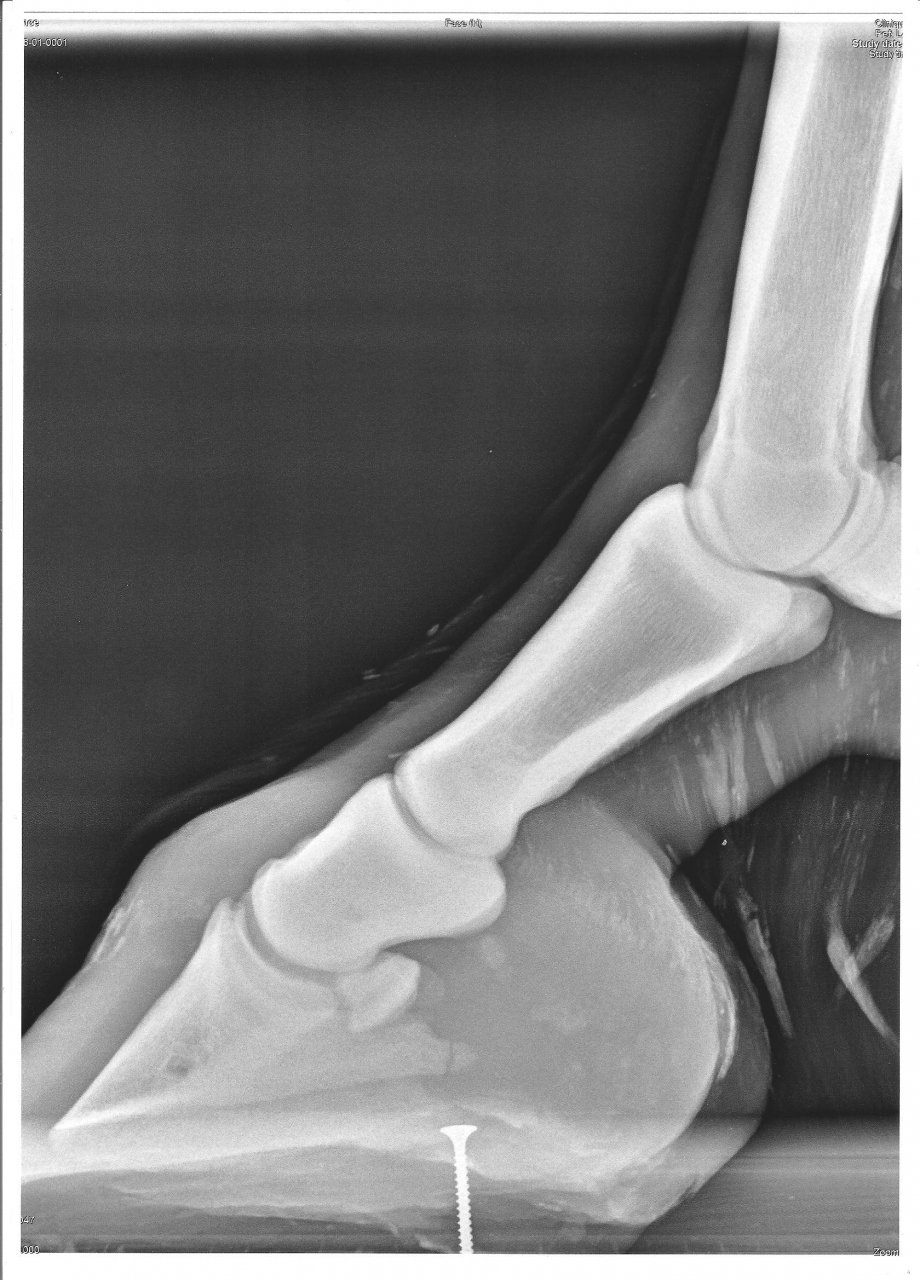

| Dire merci | Sur un fjord de 10 ans, pas gros : Il y a un moment ( découverte il y a 2 ans, mais sans doute plus ancienne ) que mon loulou à carrément une fracture du processus palmaire qui ne se ressoudera sans doute pas, découverte par hazard car on avait fait des radios pour savoir d'où venait sa boiterie et ce n'était même pas de là, il avait le garrot de bloqué... mon véto m'a donner le feu vert pour le monter et travailler normalement mais j'ai peur que le bout non ressoudé bouge à un moment ou à un autre et fasse de gros dégas... Vue que depuis il s'est encore blessé dans son parc ( déplacement de la rotule et suspition d'entorse coxo fémorale ) je ne l'ai pas encore retravailé mais maintenant il est OK pour reprendre le boulot... Alor je ne pourrais pas dire ce que çà donne au boulot... D'après ce que j'ai lue, je pence que son soucis vient d'un mauvais parrage, avant que je l'achette, ce n'était pas un MF qui le parrait... Actuellement, il est pieds nus, çà lui vat très bien ( sans travailler ), après le 15 juin je le remet au boullot tranquillement dans le but de faire un peut de TREC pour le plaisir ( donc sauter un peut ), pas en compet et surtout du dressage et de la ballade sur des chemins dur et caillouteux qui ne sont pas top pour lui... J'envisage de lui prendre des hypposandales pour un meilleur amortissement... En plus, il est fait en descendant... Tous son poid vers l'avant Y aurrait-il quelqu'un dans le même cas que moi ? Ou des personnes / vétos pouvant partager leur expériance ou avis ? Des conseils pour son travail ? J'ai entedu dire que çà arrivait fréquement en CSO... merci d'avance ! ![]() Les radios ( ce sont les premières, les dernières, je dois les redemander au véto, je ne les trouvent plus dans mon ordi...) ![]() ![]() |